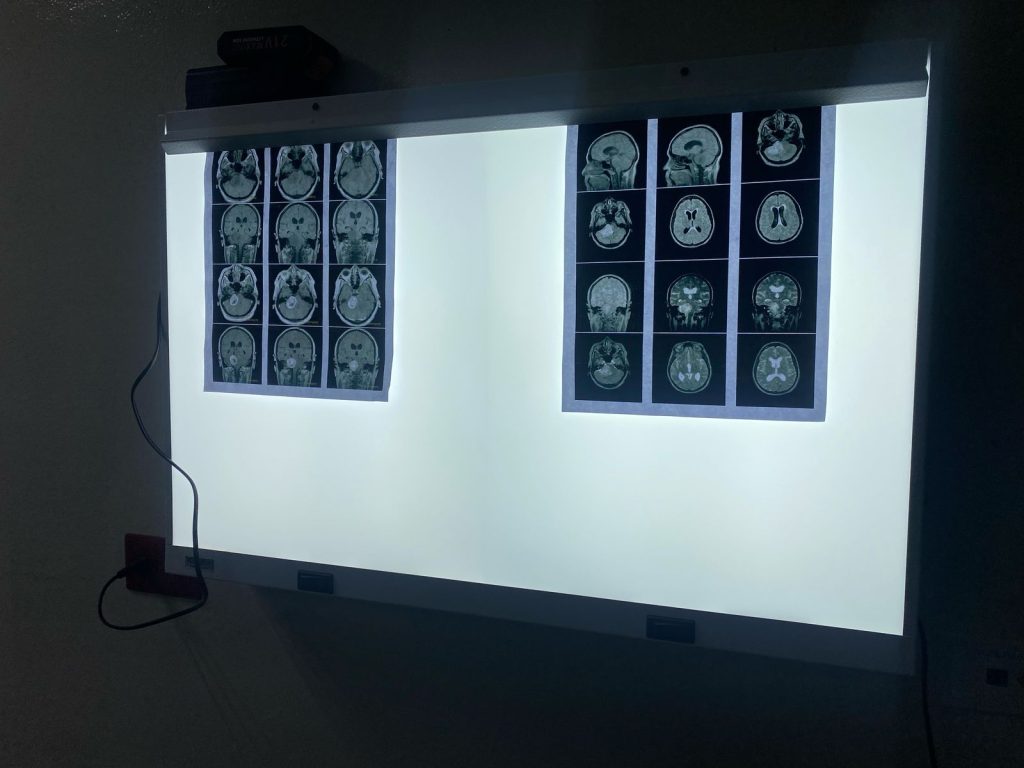

Esta intervención consiste en la colocación de una válvula especial en los ventrículos del cerebro, con el objetivo de desviar el líquido cefalorraquídeo (LCR) hacia la cavidad peritoneal. Es un tratamiento esencial para pacientes que padecen hidrocefalia, causada por condiciones como tumores cerebrales, obstrucción de los conductos, malformaciones congénitas, entre otras.